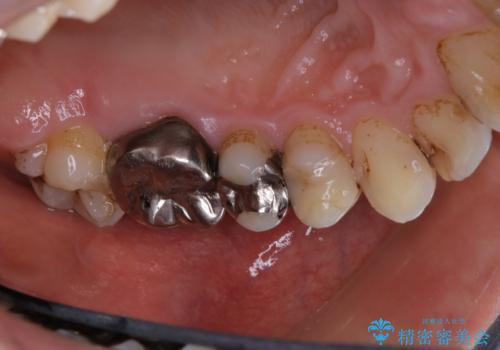

歯の表面に、茶色く色が残っている所がありますが、これは詰め物の変色によるものです。以前に、CR(コンポジットレジン)による虫歯治療がされています。

CRは経年的劣化や、着色してしまうことがあります。PMTCでクリーニングを行うと、古いCRが目立つことがあるため、気になる際は詰め替えを行います。

茶色くなっている部分が、着色なのか、劣化なのか、虫歯によるものなのかは判別が難しいことがあります。そのため、定期的にPMTCを行うことで状態の確認が的確に行えます。